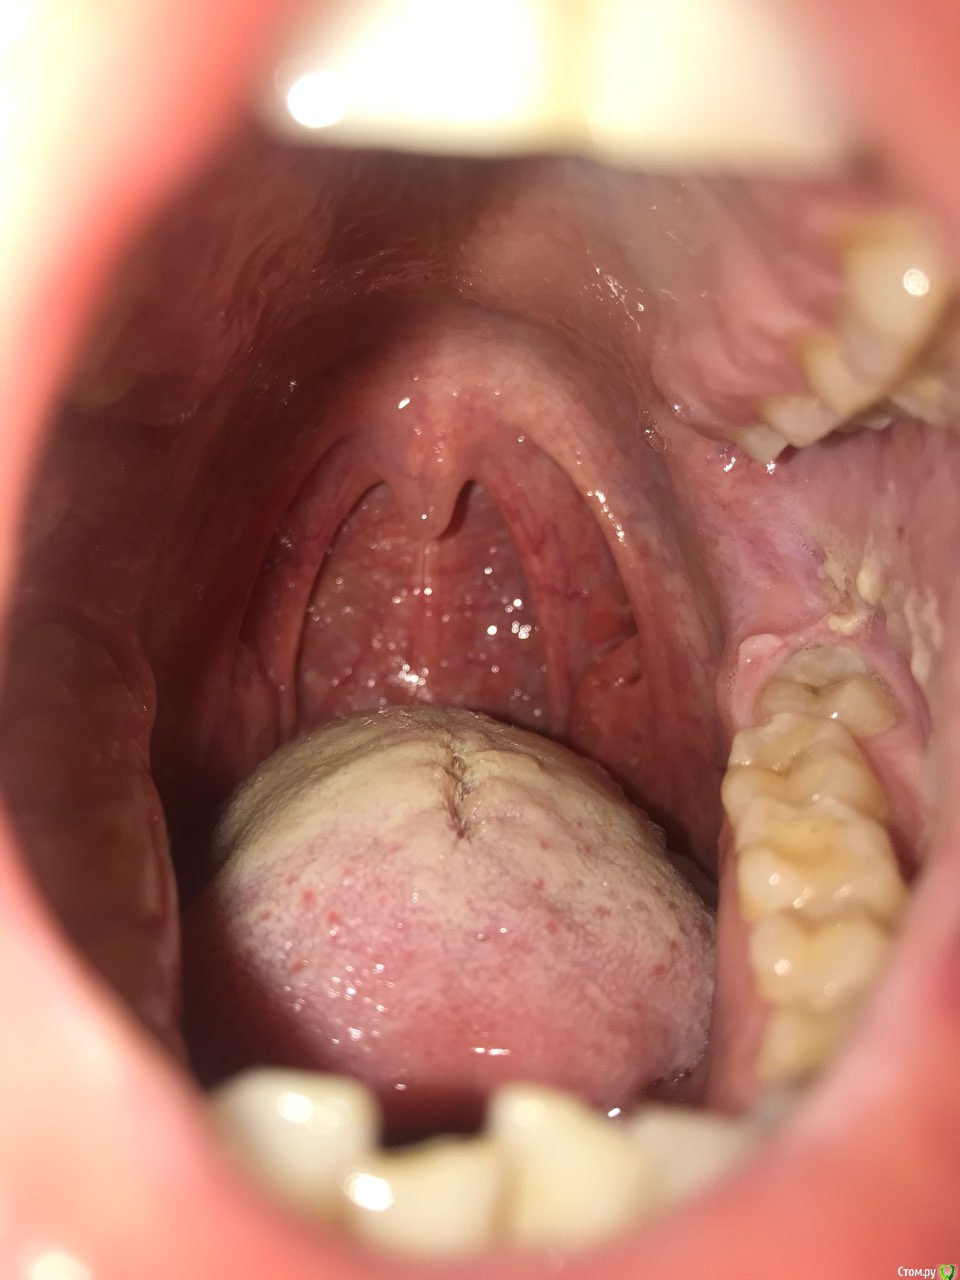

Антон Сафин Опубликовано 1 апреля, 2018 Поделиться Опубликовано 1 апреля, 2018 Последние несколько месяцев стал замечать что на стенках щек что-то стало образовываться в виде белого налета. Заглянул с фонариком увидел белые полоски + еще язык в белом налете часто, эти белые полоски на щеках не болят, не мешают, но бывает могу их кусать зубами отрывая и выплевывая как инородное тело. Что это за белые образования, опасно ли это? Как это лечить? Где-то в интернете наткнулся что это называется - Лейкоплакия, так ли это? Ссылка на комментарий

Борис80 Опубликовано 1 апреля, 2018 Поделиться Опубликовано 1 апреля, 2018 (изменено) поправьте гигиену полости рта для начала,в этих местах ( в области линии смыкания зубов) очень часто встречаются участки с подобным эпителием, с заболеваниями ЛОР органов часто сталкиваетесь? Если заметных улучшений не отметите, обратитесь очно к стоматологу Изменено 1 апреля, 2018 пользователем Борис80 Ссылка на комментарий

Антон Сафин Опубликовано 1 апреля, 2018 Автор Поделиться Опубликовано 1 апреля, 2018 поправьте гигиену полости рта для начала,в этих местах ( в области линии смыкания зубов) очень часто встречаются участки с подобным эпителием, с заболеваниями ЛОР органов часто сталкиваетесь? Если заметных улучшений не отметите, обратитесь очно к стоматологу Спасибо за ответ!А каким образом можно "поправить" гигиену, расскажите подробнее что имелось ввиду. Лор заболевания хронические, переодически обостряются (тонзиллит, фарингит) как это может влиять на образование белого налета на щеках? А улучшений и не будет, нужно понять что это за явление и как оно называется, потом применить комплекс лечебных и профилактических мер. Ссылка на комментарий

dentikl Опубликовано 2 апреля, 2018 Поделиться Опубликовано 2 апреля, 2018 белые полоскиВы курите?Если да,то сколько сигарет в день? Ссылка на комментарий

Антон Сафин Опубликовано 2 апреля, 2018 Автор Поделиться Опубликовано 2 апреля, 2018 Вы курите?Если да,то сколько сигарет в день?Курю, в среднем 4-7 сигарет в день, могу несколько дней не курить вообще, пытаюсь бросить. Ссылка на комментарий

dentikl Опубликовано 2 апреля, 2018 Поделиться Опубликовано 2 апреля, 2018 пытаюсь бросить. если беленькое попробовать аккуратно счистить,что будет(на маленьком участке) Ссылка на комментарий

Антон Сафин Опубликовано 3 апреля, 2018 Автор Поделиться Опубликовано 3 апреля, 2018 если беленькое попробовать аккуратно счистить,что будет(на маленьком участке)Сложно сказать, но скорее не счищается, такое ощущение что это старые части слизистой такое может быть? Ссылка на комментарий

Антон Сафин Опубликовано 5 апреля, 2018 Автор Поделиться Опубликовано 5 апреля, 2018 стоматологу-терапевту.желательно специализаия-слизистыеСходил к терапевту и хирургу, терапевт сказал что этот белый налет что-то странное и отправил к хирургу, а он в свою очередь сказал что это не страшно, нужно удалять "восьмерки" и править прикус, мол из-за этого я прикусываю щеки, странно это, учитывая что про "проблемы" с зубами я знал давно и налета не было. К кому еще идти? п.с. зубы буду делать в ближайшее время. Ссылка на комментарий